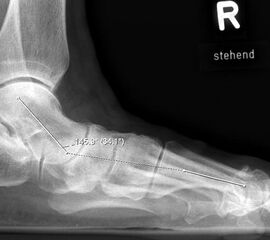

Auf der seitlichen, stehenden Aufnahme des Fußes wird ebenfalls der laterale Talo-Metatarsale I Winkel (Abb. 6 d) gemessen und so das kollabierte mediale Längsgewölbe dokumentiert. Auch hier gilt ein Talo-Metatarsale I Winkel von > 5° (nach plantar konvex) als pathologisch 21. Der Kollaps findet dabei meist im Talonaviculargelenk, seltener in der Naviculocuneiform-Gelenkreihe statt. Instabilität und Arthrose im 1. TMT sollten ausgeschlossen oder bei der Operationsplanung mit einbezogen werden. Weitere wichtige radiologische Messungen zur Beurteilung der Planovalgus-Statik und Progression der Deformität sind der laterale talo-calcaneare Winkel (Abb. 6 e) und der Abstand des Os cuneiforme-Unterrandes zum Untergrund (Abb. 6 f, Cuneiform height, 22. Eine anteriore Translation des Talus auf dem Kalkaneus findet man sowohl auf der ap, als auch auf der seitlichen Aufnahme des Fuβes mit Aufhebung der Cima-Linie.